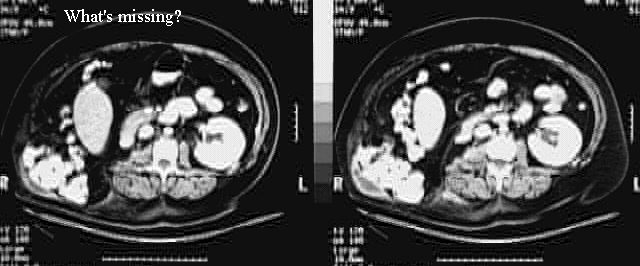

Abdomen - Kidney Removed

Abdominal wall herniation - posterolaterally.